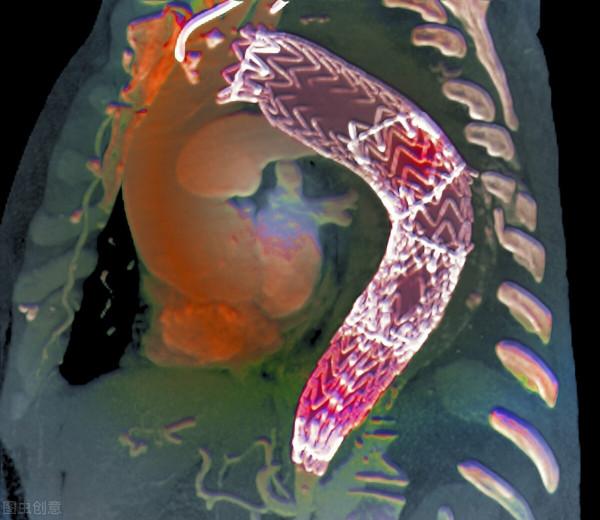

發現動脈瘤之後患者並沒有太在乎。可實際上,主動脈瘤的病人,血壓就應該降得更低一些,收縮壓要降到120mmHg以下才好。因為動脈瘤的血管壁,受損傷變薄了,血壓高就加重損害,有破裂的風險。果然,動脈瘤逐漸增大了。這樣,在診斷治療高血壓的第8個年頭,患者做了主動脈動脈瘤的帶膜支架封堵。

主動脈放支架也要用碘造影劑。這次給患者選了最新一代的碘造影劑碘克沙醇,商品名“威視派克”,也在手術前後進行了“水化治療”保護腎臟。可是很無奈,腎臟損害已經遏制不住。

於是,動脈瘤封堵術後,患者腎功能每況愈下。就在大動脈支架植入近1年的時候,患者因為“尿毒症”、醫學上叫做終末期腎病,進行了血液透析。

之後數月,患者又出現了季肋部、也就是下胸部的疼痛。一檢查,發現原來主動脈放支架的下段血管,血管壁裡面撕裂了,形成了夾層動脈瘤。但是,經過多家會診、反覆討論,已經不適合做什麼特殊處理了,就是內科保守治療,繼續控制血壓,收縮壓也就是高壓在120mmHg以下。這已經是診斷治療高血壓的第9個年頭了。